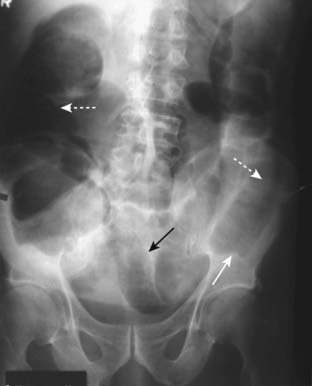

Figure 14-2 Generalized adynamic ileus, supine (A) and upright abdomen (B).

There are dilated loops of large (solid white arrows) and small bowel (dotted white arrows) with gas seen down to and including the rectum (solid black arrows). The patient had undergone colon surgery the previous day.